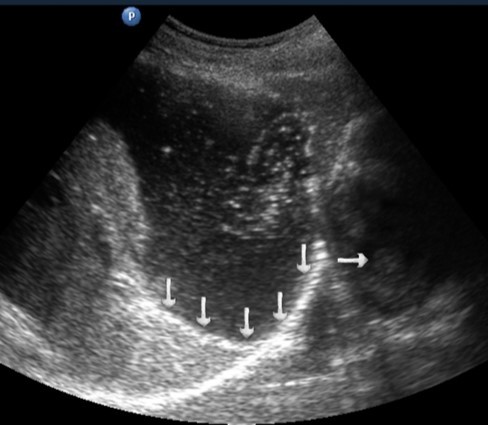

T3 stage of polypoid form was recorded in one case, ulcerative form – in 11 cases, infiltrative ulcerative forms – in 21 cases and diffused infiltrative forms – in 8 cases. The Sonographic features of infiltrative ulcerative form of gastric carcinoma was shown as local uneven thickening of the stomach wall with a length of up to several centimeters with intermittent images and ulceration of the mucosa (Figure 11). The Ulcerative form of gastric carcinoma was shown as a raised margins surrounded by a thickened gastric wall with irregular margins (Figure 12). Gastric carcinomas of diffuse infiltrative form is illustrated as a diffuse thickening of the muscle layer, a smooth contour, discontinuous mucosal image without ulceration and involvement of the serous membrane in the process (Figure 13).

Figure 11.Gastric carcinomas of ulcerating infiltrating forms in the anterior wall of the stomach body of stage T3.

Figure 12.Gastric carcinomas of ulcerating forms in the anterior wall of the stomach body of stage T3. Tumor is manifested with raised margins surrounded by a thickened gastric wall without clear margins.

Figure 13.Gastric carcinomas of diffuse infiltrative form in the posterior wall of the stomach body of stage T3. The tumor is manifested by diffuse thickening of the muscle layer, a smooth contour, discontinuous mucosal image without ulceration and involvement of the serous membrane in the process. An enlarged, altered lymph node of low echogenicity, round shape, without differentiation of the peripheral and central part, is visualized behind the stomach.

Distal gastric cancer was observed in 24 (39,3%) cases and contributed to the development of pyloric stenosis: in 6 (9,8%) cases it was compensated, in 18 (29,5%) – was sub compensated. The layers of the wall were not differentiated in all patients with sub compensated pyloric stenosis. In the case of compensated pyloric stenosis, the thickness of the affected area was 10,2±2,9mm, the length was 27,1±6,2mm, the diameter of the pylorus was 8,3±0,8mm (Figure 14). Among patients with sub compensated pyloric stenosis, the thickness of the stomach wall was 19,8±4,1mm, the length was 43,6±4,5mm, the pyloric diameter was 4,3±1,1mm (Figure 15).

Figure 14.Gastric carcinomas of diffuse infiltrative form in the atrium of T2 stage. Compensated pyloric stenos. On an empty stomach in the cavity of the stomach is determined an a small amount of fluid. The diameter of the pyloric canal more than 7 mm.

Figure 15.Distal gastric carcinomas of diffuse infiltrative form of T3 stage. Sub compensated pyloric stenos (arrows). The thickness of the anterior wall of the stomach is 9,13 mm, extent of the affected area – 7,84 cm. On an empty stomach in the cavity of the stomach is determined an a large amount of fluid. The diameter of the pyloric canal is about 6 mm.